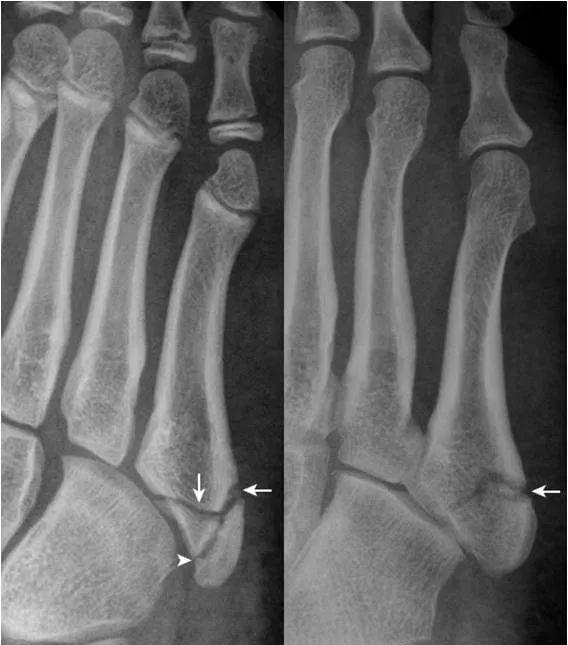

31.第5跖骨粗隆骨折:

第5跖骨粗隆处见横行、纵向透亮线,横行透亮线(箭)为骨折线,纵向透亮线(箭头)为骨骺与骨间的软骨连接投影。撕脱骨折线为横行走向是与骨骺连接线的重要鉴别点。(右图,女,5岁;左图,男13岁)